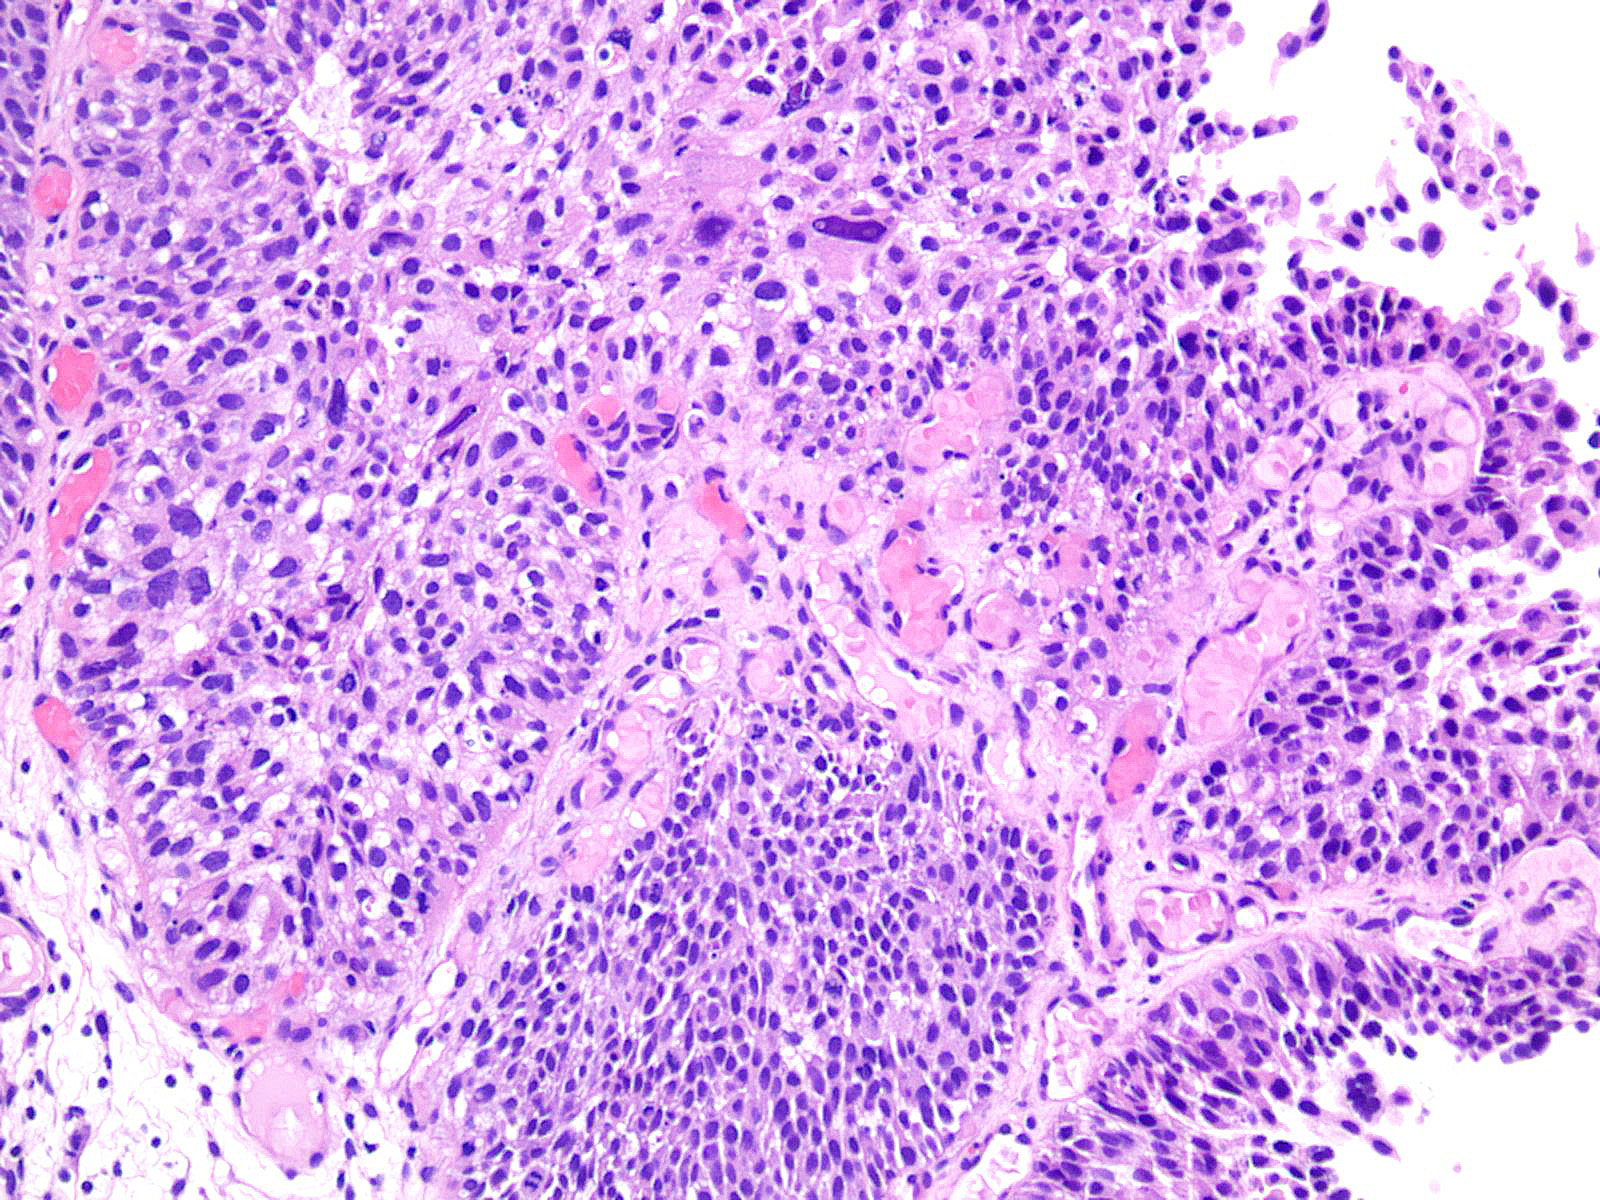

Bladder Papillary Lesions

Case ID: 193